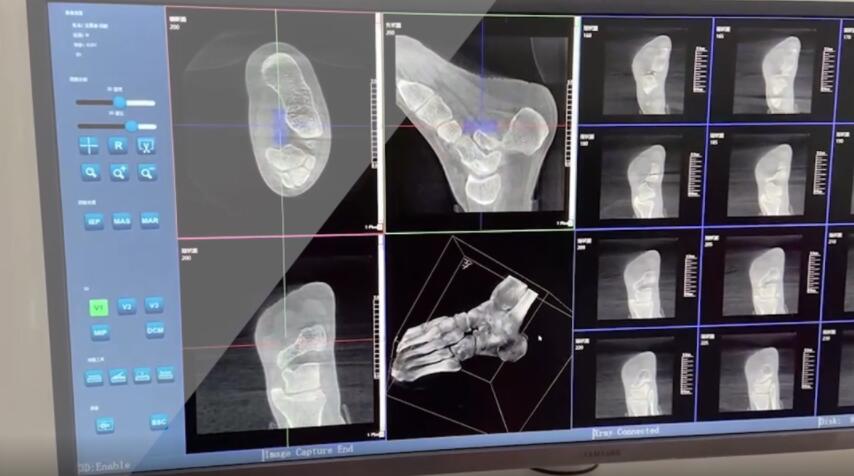

在術(shù)前,我們需要做三維掃描的CT檢查,我們必須要有CT的片子,還要有三維的重建。

在術(shù)中,我們?cè)趺慈ヅ袛嚓P(guān)節(jié)面平不平整呢?常規(guī)的正側(cè)位影像是不能判斷的。有些醫(yī)生為了準(zhǔn)確的判斷,可能會(huì)選擇做開(kāi)放性的手術(shù),把關(guān)節(jié)暴露出來(lái),在眼睛的直視下判斷關(guān)節(jié)面平不平整。但是關(guān)節(jié)全部打開(kāi),無(wú)疑增加了病人的創(chuàng)傷,而且增加了患者的恢復(fù)時(shí)間。所以如果在術(shù)中我們有三維影像的支持,對(duì)醫(yī)生做手術(shù)而言就會(huì)事半功倍,而且能夠大大的增加手術(shù)準(zhǔn)確度,增加患者術(shù)后的預(yù)后。所以在術(shù)中有三維影像的支持是非常必要的!

三維影像 看透關(guān)節(jié)內(nèi)骨折的“眼睛”